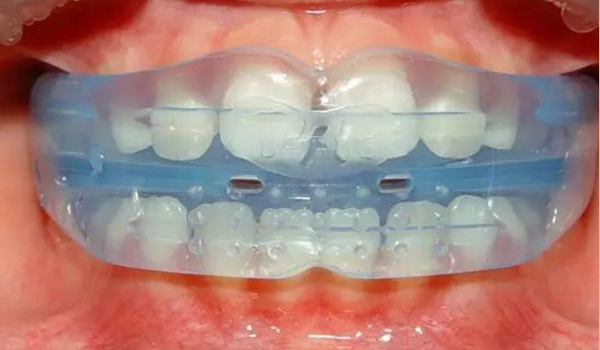

3D數碼隐形正牙

技(jì )術優勢

美觀時尚 · 外觀透明隐形

效果預知 · 可(kě)見正牙效果

方便省時 · 可(kě)自行摘戴